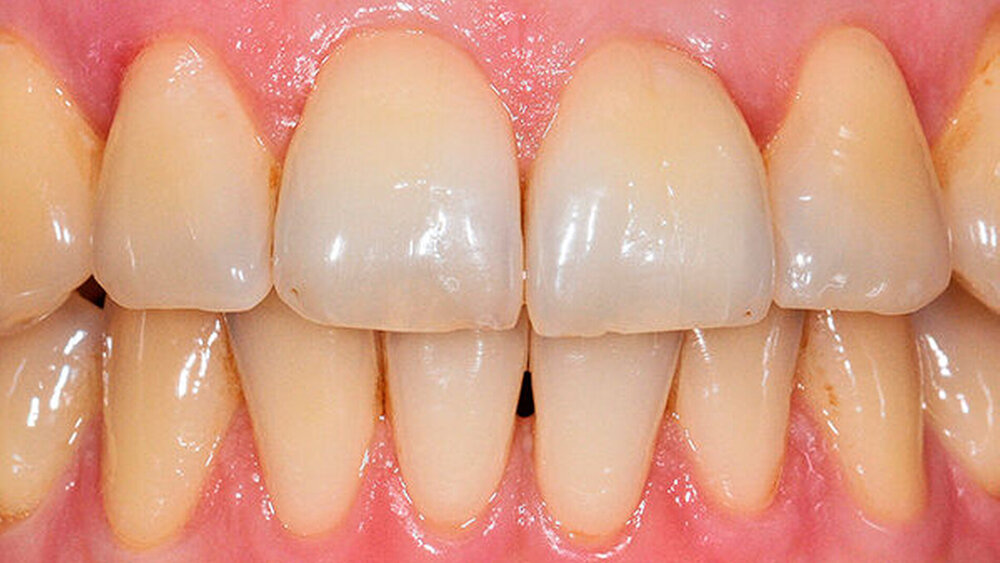

Ergebnis: Mithilfe der zusätzlichen Anwendung des mit Chlorhexidin beschickten Medikamententrägers konnte im Rahmen der gewählten unterstützenden Parodontitistherapie die parodontale Tasche lokal erfolgreich behandelt werden. Dies ist auch im Röntgenbild erkennbar (Abb. 4), das den radiologisch konsolidierten Knochenanbau am distalen Bereich deutlich zeigt.